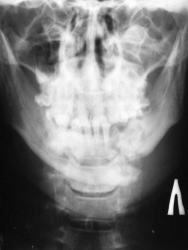

А это визави.

Ваше мнение коллеги.

на мой взгляд здесь перелом суставного отростка